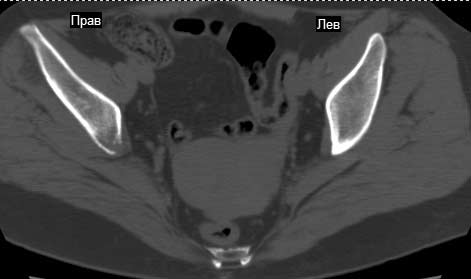

Сохранная по соматической патологии женщина ,47 лет. В 1996 г. установлен диагноз- cr левой молочной железы Т2N1Mo (2б)- проведено комплексное лечение- мастэктомия по Холстеду, ДГТ, 5 курсов ПХТ по схеме CMF. Сейчас менопауза уже 6-7 лет. В декабре 2004 года на профилактической остеосцинтиграфии с Тс99- выявлен единичный очаг повышенной фиксации препарата в зоне правой седалищной кости, рекомендована Рентгенография костей таза, выполнена- без патологии. УЗИ брюшной полости и Р-графия легких от конца апреля 2005 года - без патологии. Приблизительно 3 месяца назад появился болевой синдром в правом т/бедренном суставе с тенденцией к усилению. На рентгенограмме таза от мая 2005 года по заключению Рентгенолога очагов остеодеструкции не выявлено. Сегодня сделал ей Кт костей таза (картинки в приложении)- очаг деструкции в правой седалищной кости в зоне крыши вертлужной впадины.Что можно и нужно сделать? Жду советов, мнений, предложений по дальнейшей тактике ведения больной. С уважением, Корнев А.В.